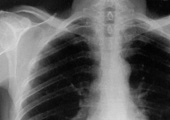

Del profesor Enrique Baca aprendí la necesidad de distinguir entre signos y síntomas como datos de partida a valorar para un correcto diagnóstico. Los signos son objetivos y mensurables (la temperatura del individuo, por ejemplo); los síntomas, por el contrario, son subjetivos y han de ser interpretados “en el discurso del paciente” (así, el dolor). Ocurre con frecuencia que un síntoma no constituye un indicio suficiente para formular un diagnóstico seguro, por lo que procede indagar la posible existencia de signos que lo confirmen. El dolor puede ser síntoma de un infarto de miocardio, pero sólo una exploración enzimática y electrocardiográfica permiten confirmarlo o descartarlo. Algo semejante sucede en el terreno económico y social.